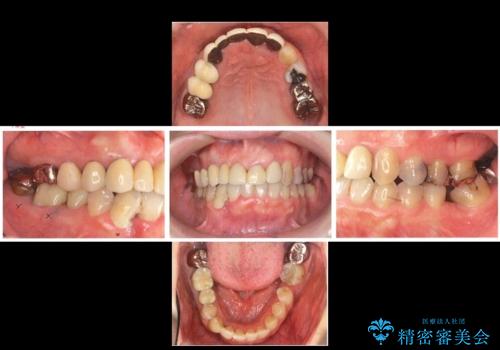

- 50代女性

- 2年

- 10-30回

- 全体的な虫歯治療、根管治療、および歯周病治療を行いました。

歯周病治療につきましては歯周ポケット除去のために歯周外科処置(APF)を行っています。

左下6の欠損については左下7はワイヤー部分矯正でアップライトを行い、補綴スペースを確保しています。

右下犬歯は歯周病の進行が重度のため、やむなく抜歯をし、骨増生後にインプラント埋入を行っています。